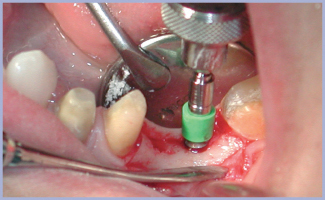

Dopo avere allestito il lembo a spessore totale (figg. 2, 3), si preparano due alveoli chirurgici, uno per l’impianto che sostituirà la radice mesiale, orientato in modo tale da risultare in asse con i carichi funzionali che si creano nella fase di entrata del ciclo masticatorio ed uno che sostituirà la radice distale, orientato in asse con i carichi funzionali che si creano nella fase di uscita. Poiché è necessario intaccare la corticale con estrema precisione, si inizia la preparazione con una fresa a palla montata su turbina (figg. 4, 5); si prosegue con il protocollo classico (figg. 6-14). Si inseriscono gli impianti, si assemblano i relativi tappi (figg. 15-19) e si sutura (fig. 20) secondo il protocollo bifase. Dopo tre mesi, quando l’osteointegrazione ha raggiunto una maturazione sufficiente ad assicurare la stabilità primaria degli impianti, si interviene con il secondo momento chirurgico per posizionare i tappi di guarigione e creare i condotti mucosi (figg. 21-24) che si epitelizzeranno in circa dieci giorni. Segue la presa delle impronte mediante transfer da impronta (figg. 25-28). Il tecnico assembla gli analoghi da gesso sui transfer, sviluppa i modelli, monta i monconi sugli analoghi ed esegue il fresaggio (fig. 29). In studio si verificano i monconi (fig. 30) e si rimandano in laboratorio per la preparazione delle cappette (fig. 31) e la relativa ceramizzazione (fig. 32).

- Fig. 15

- Fig. 16

- Fig. 17

- Fig. 18

- Fig. 19